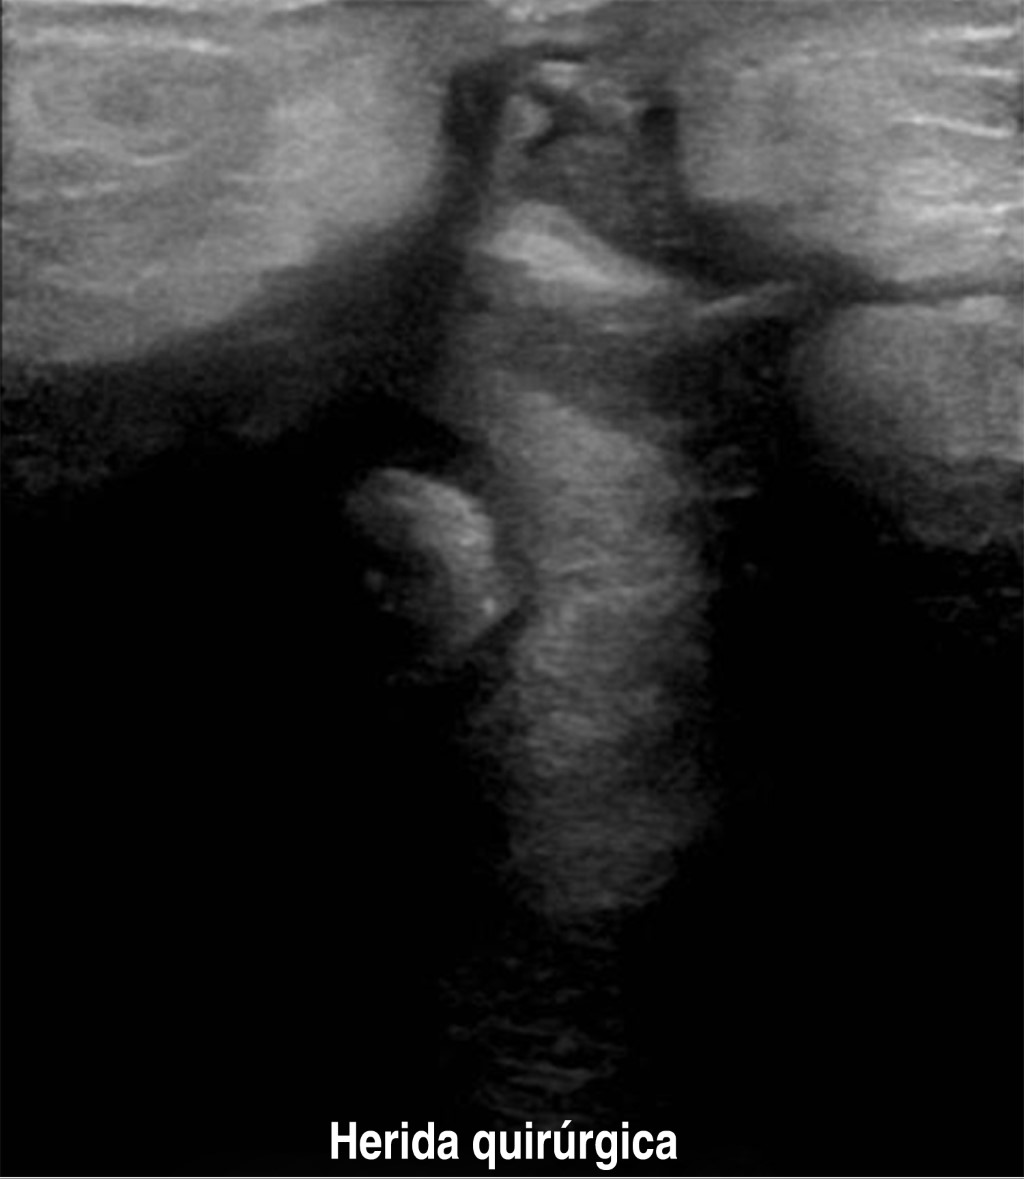

Paciente femenino de 40 años de edad, gesta cuatro, partos tres, con antecedente de estenosis valvular aórtica desde 2017 con manejo quirúrgico a base de colocación de prótesis valvular y acenocumarina hasta el diagnóstico de su último embarazo, durante el cual se suspende anticoagulante oral e inicia enoxaparina. Inicia padecimiento actual al ingresar al servicio de obstetricia con reporte de edad gestacional de 28.5 semanas de gestación (SDG) por última menstruación y de 29.4 por fetometría. Se diagnostica preeclampsia con datos de severidad, por lo que se decide realizar cesárea tipo Kerr y oclusión tubaria bilateral con técnica de Kroener, reportando 350 cm3 de sangrado, obteniendo producto único vivo, masculino, 31.5 semanas por Capurro, Apgar 7/8, con labio y paladar hendido. Egresa al quinto día requiriendo transfusión de hemoderivados en su postquirúrgico inmediato. Veintiún días después reingresa por sangrado abundante y fétido a través del abordaje quirúrgico, se hace curación y se evidencia defecto de pared abdominal, por lo cual se decide realizar ultrasonido, con hallazgos de defecto de pared anterior del abdomen en porción cefálica de la herida a través del cual protruyen asas intestinales (Figuras 1 y 2), en tomografía de abdomen se identifica colección heterogénea no medible en tercio medio y caudal de herida a nivel del plano subcutáneo, así como colección de pared gruesa en cavidad pélvica y fosa iliaca izquierda (Figura 3).

Figura 1